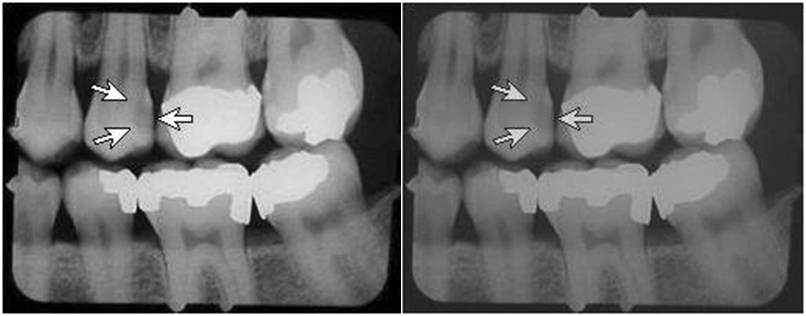

Digital dental radiography uses x-rays the same as film imaging and also results in x-ray doses to your patients and staff. Digital offers the potential for significant reductions in x-ray dose. However, it has been our experience that about 25% of the offices that switch to digital dental are using doses similar to or higher than D-speed film! D-speed film usually requires a dose of about 200 mrad. Digital doses should be on the order of 50 to 75 mrad, a reduction in dose of 60 to 75%.

You should have your present doses measured, a service provided by DIQUAD, LLC via mail through the DIQUAD website image upload system. Your present exposure time should be about 25% to 45% of the exposure time you were using with D-speed film. For example, if your exposure time was 300 msec (0.3 sec) for D-speed film you should be using about 75 to 120 msec (0.075 to 0.12 sec) for digital imaging. If you were using E-speed film and an exposure time of about 200 msec (0.2 sec), your digital exposure times should also be about 75 to 120 msec (0.075 to 0.12 sec).